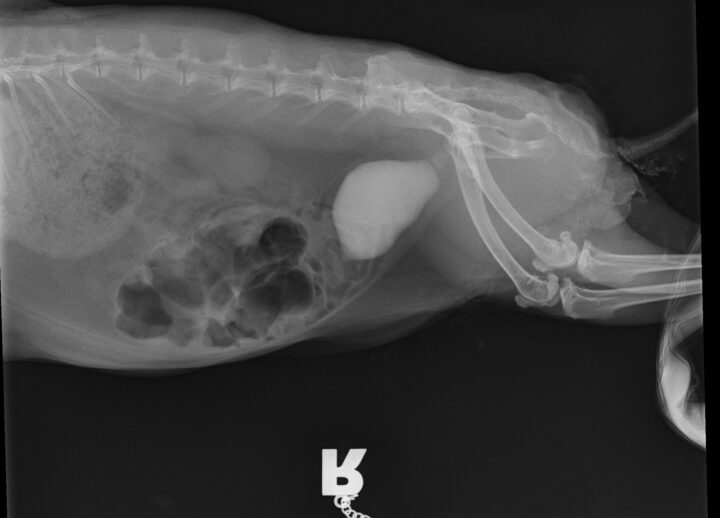

Diagnosis is typically based on clinical signs, physical examination, urinalysis and imaging. The urine may appear cloudy or contain visible sediment. Radiographs can help assess the amount of sludge present and rule out other issues such as urolithiasis (Figure 2). Urinary ultrasound is another useful tool, providing a more detailed view of the bladder wall and sludge accumulation.

The clinical signs of urolithiasis in rabbits include haematuria, dysuria, frequent urination and stranguria. In some cases, the stones can cause a complete obstruction of the urinary tract, which is a medical emergency (Circella et al., 2021). Diagnosis is confirmed through radiographs, where the stones will appear as radiopaque structures, or via ultrasound, where uroliths result in acoustic shadowing.

Common symptoms of urolithiasis in guinea pigs include stranguria, haematuria and signs of discomfort or pain when urinating, such as vocalisation. Diagnosis of urolithiasis in guinea pigs is similar to diagnosis in rabbits, using physical examination, urinalysis and imaging techniques, such as radiographs or ultrasound. Radiographs will often reveal the presence of stones (Figure 4), though small stones may be missed if they are not radiopaque. Ultrasound can be particularly useful for detecting smaller stones or those located in the kidneys or ureters.